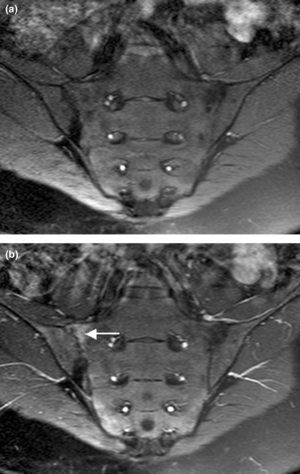

التشخيص